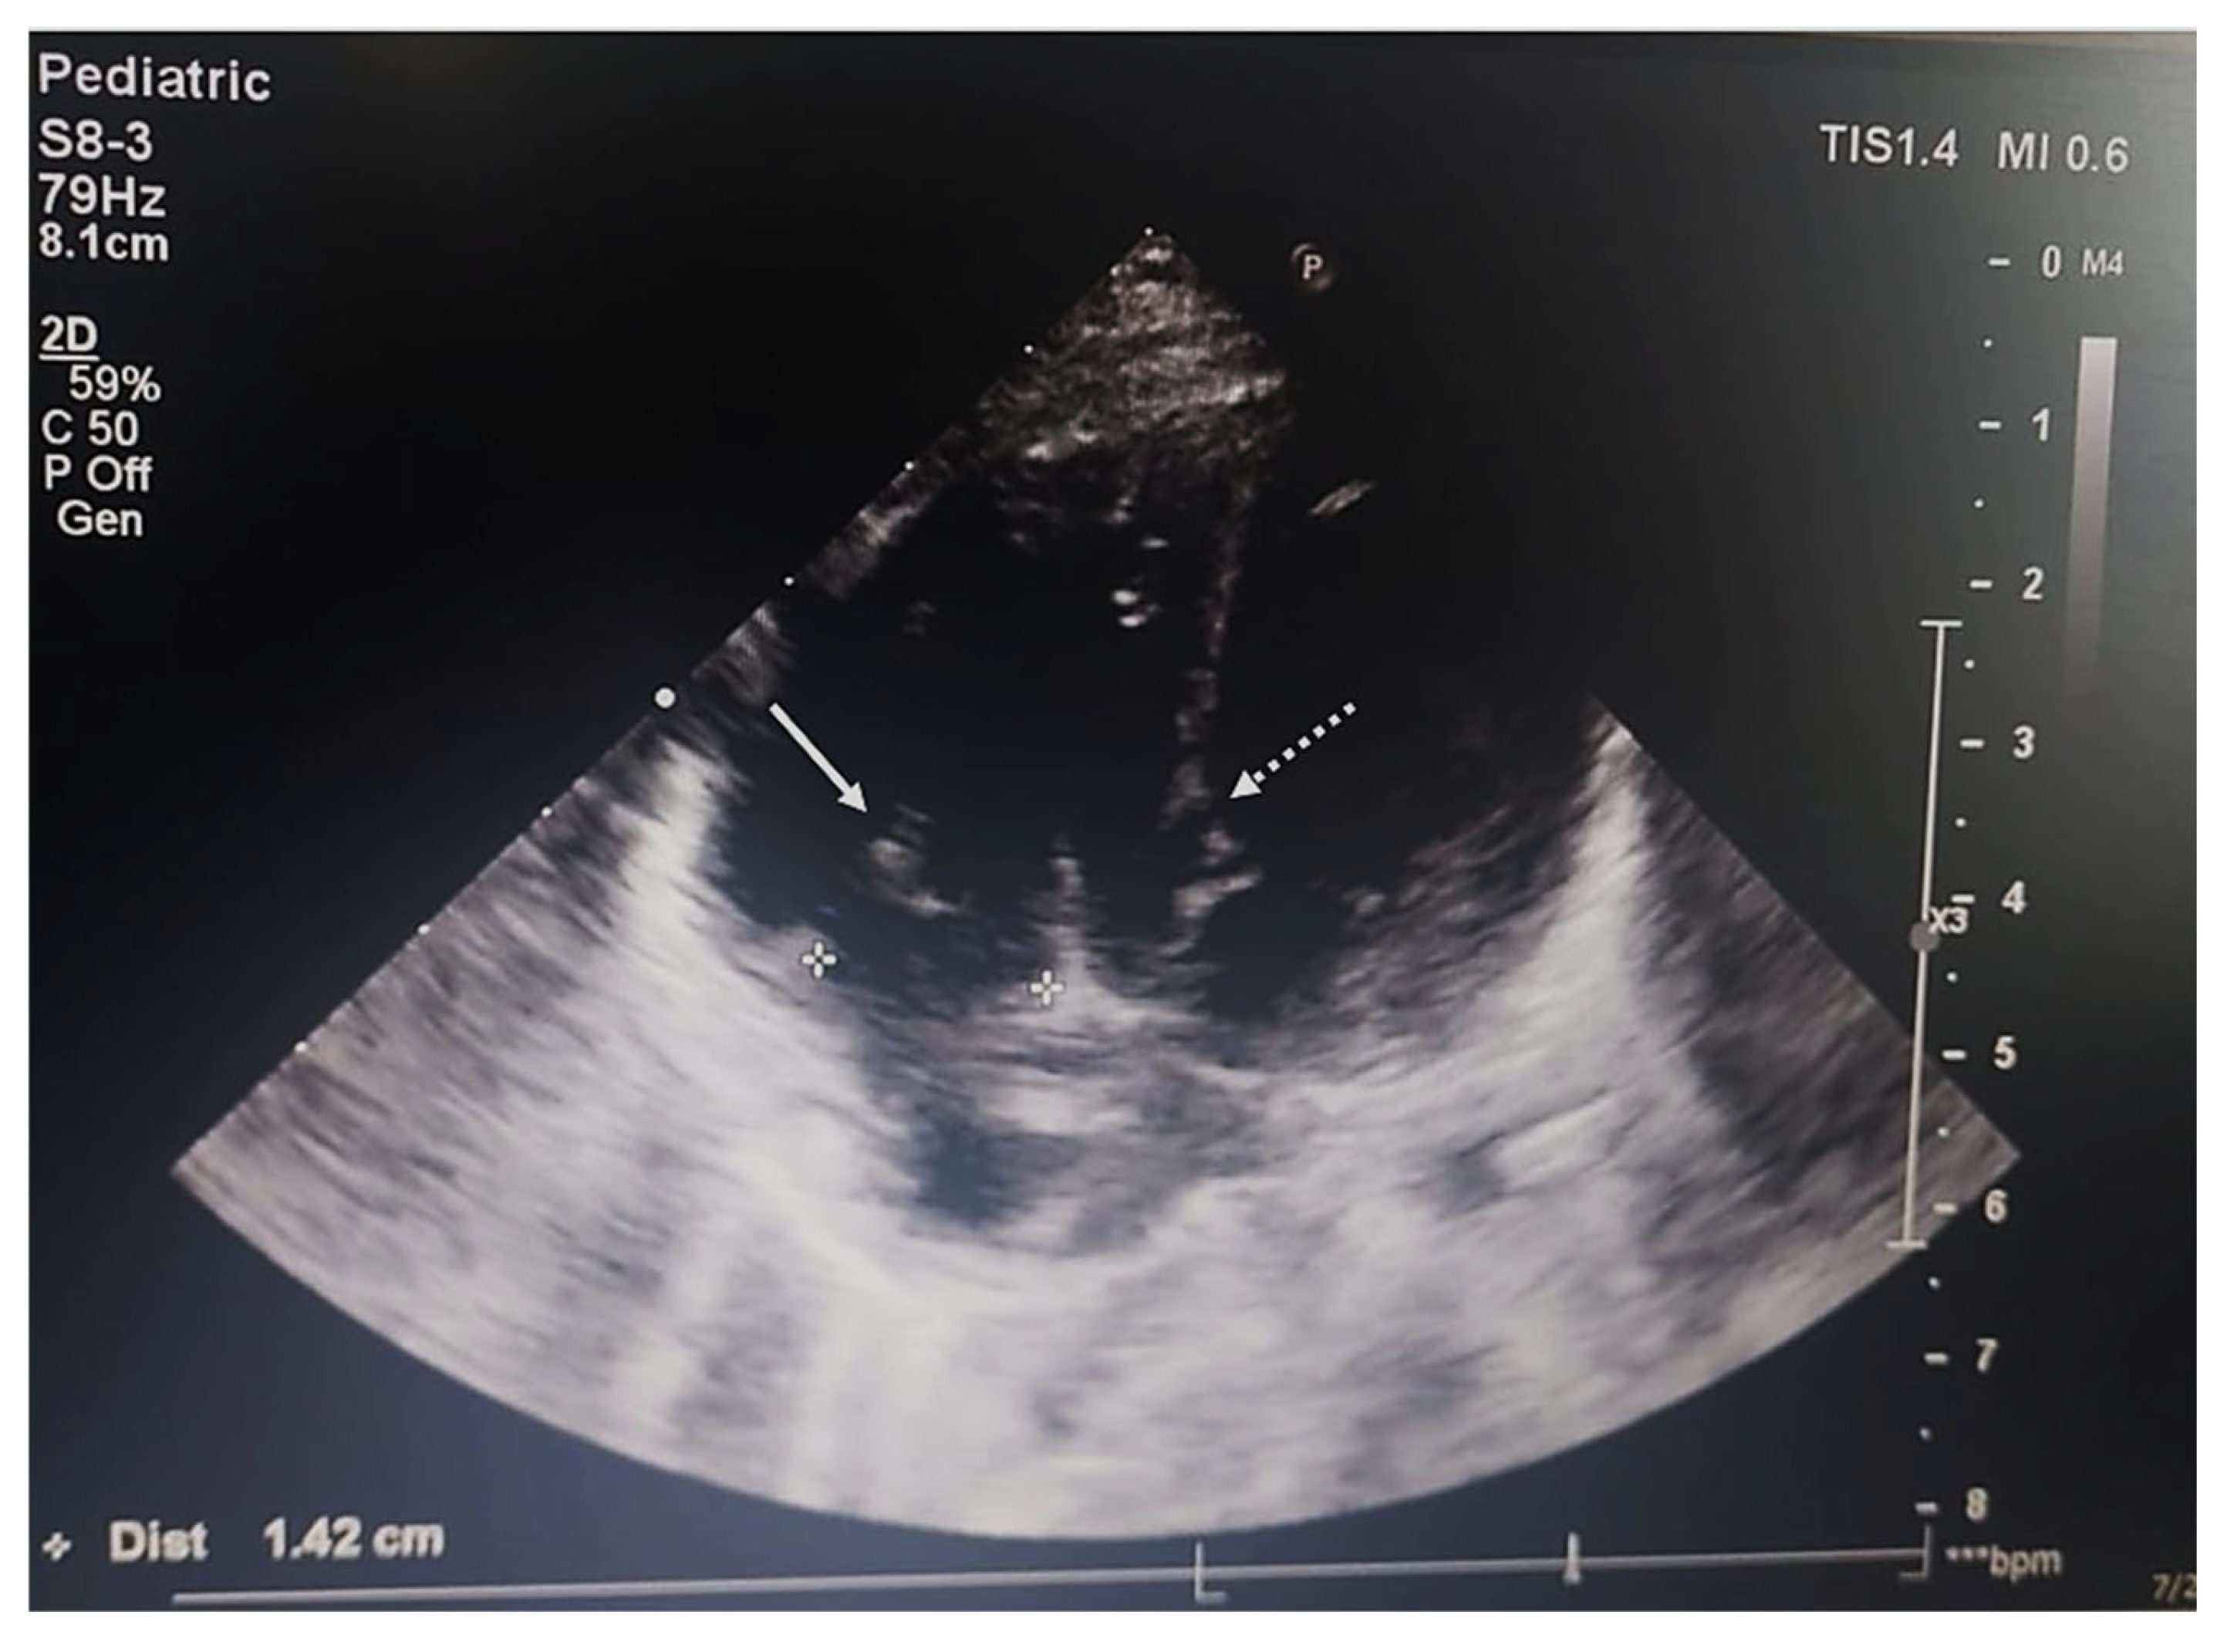

2.4. Imaging and Endoscopic Examinations